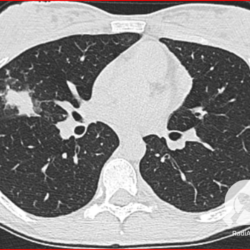

Os agentes etiológicos infecciosos são variados (bactérias, vírus, fungos, parasitas…), mas o que ocorre nos pulmões durante uma infecção por qualquer tipo de agente é a substituição do ar alveolar por secreção (pus, muco, eventualmente sangue ou necrose…) e com isso a manifestação radiográfica vai ser a mesma já que todas estas secreções apresentam a mesma densidade radiográfica: partes moles.

E o nome dado a esta alteração radiográfica que corresponde à substituição do ar alveolar por líquido é a consolidação alveolar.

Uma consolidação alveolar é, por definição, uma opacidade (imagem densa, branquinha) homogênea ou às vezes heterogênea (pela presença de calcificações ou cavidades), de limites mal definidos, exceto quando toca a pleura da parede ou das cissuras pulmonares. É um termo usado tanto em radiografia, como em tomografia computadorizada. Na tomografia, um outro termo é usado: vidro fosco, que é uma opacidade (branquinha mas não tanto como a consolidação), que borra o pulmão mas deixa ver os vasos de permeio (igual bigode de adolescente: dá pra ver todo o fundo).

Nós vamos mostrar aqui um pequeno apanhado de pneumonias de variados agentes, em diversos segmentos e lobos pulmonares, com extensões variadas. O objetivo é identificar o padrão radiológico de consolidação alveolar e não determinar o agente infeccioso, isso vai ser assunto para mais adiante. Aliás já antecipo que é fundamental saber localizar a lesão, porque alguns destes bichos gostam de determinados segmentos, alguns tumores também têm as suas preferências, então localização é fundamental. Se localização não fosse importante, um apartamento na beira do mar sairia o mesmo preço de um apartamento de frente pra BR-101, concordam?